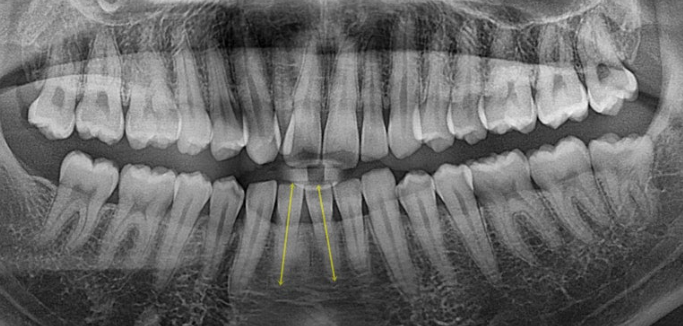

치료 전 후 파노라마 엑스레이를 보면 블랙트라이앵글의 원흉이었던 아래 앞니 치축 기울어짐이 해소된게 보입니다.

위 앞니 치축도 평행해졌습니다.

<인비절라인으로 뿌리 이동은 안된다.>는 잘못된 말입니다.

1년 8개월간의 치료 기간동안 치근흡수는 없습니다.

아래 앞니 블랙트라이앵글은 치축의 개선과 소량의 치간삭제로 사이즈를 줄였습니다.